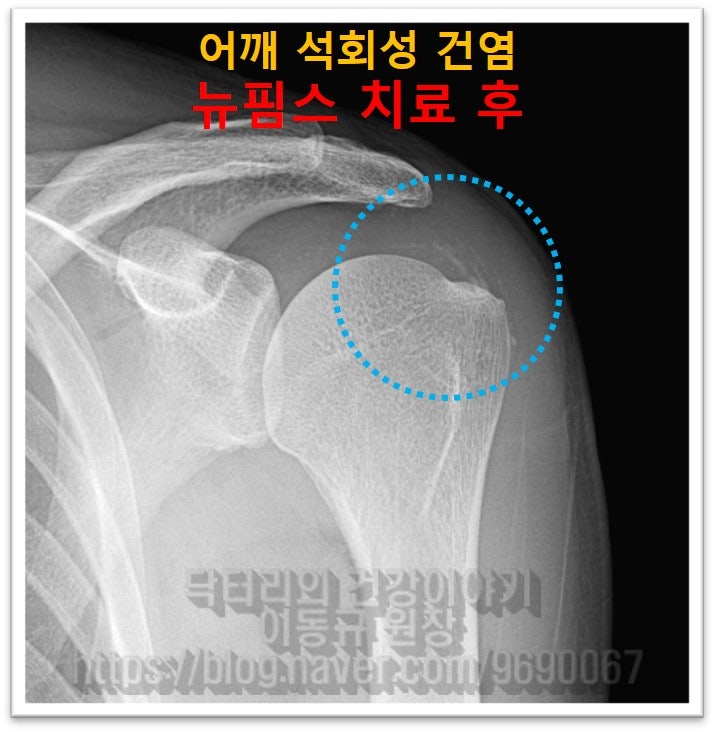

이렇게 상당히 큰 석회라도 충분히 비수술적 치료를 할 수 있습니다. 그래서 뉴핌스치료(석회분쇄흡입술)를 시행하였습니다.

남아있는 석회는 향 후 충격파 치료를 추가적으로 시행하여 흡수를 시키면 됩니다.

환자분은 시술하고 난 후 정말 거짓말 처럼 통증이 사라졌다고 좋아 하셨습니다. 석회성 건염은 크기가 크다고 수술해야하는 것이 아닙니다. 크기가 크더라도 충분히 비수술적으로 제거할 수 있습니다. 물론 비수술적으로 석회를 제거하기 위해서는 숙련된 기술과 충분한 경험이 있어야 합니다. 석회의 양상과 크기, 위치에 따라서도 석회분쇄흡입술이 달라질 수 있기 때문입니다.